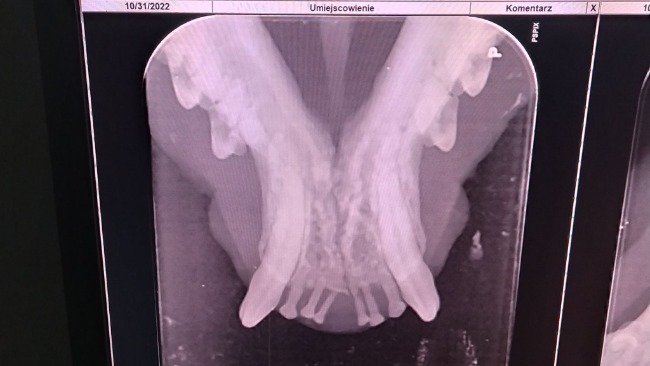

Pod naszą opieką znajduje się bezdomny kociak, który zmaga się z przewlekłym zapalniem przyzębia. Pomimo leczenia, płukanek, lekow na podnoszenie odporności stan jamy ustnej nie uległ zadnej poprawie. Dziś u kociaka przeprowadzono zabieg usunięcia niektórych zębów. W jak złym były stanie i jaki powodowały ból obrazują to zdjęcia rtg. Bardzo proszę o pomoc w opłaceniu rachunku za dzisiejszy zabieg usunięcia zebów w narkozie wziewnej u kotka Miałka na kwotę 590 zł. Za każdą wplatę z całego serca dziękuję!